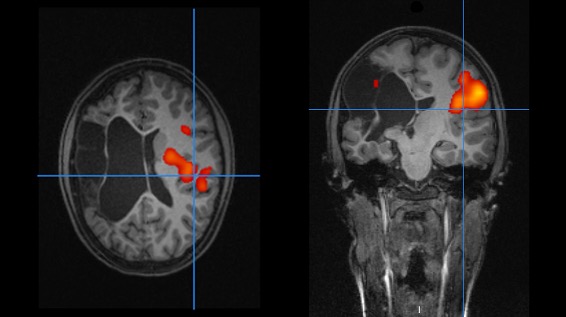

The present project focuses on the organization and localization of language processing in children with focal brain lesions acquired during language development and aims at investigating the relationship between behavioral language abilities and cerebral organization of the semantic language network. To achieve this goal, children with ischemic stroke acquired during development of language and healthy controls are included in the study. Behavioral language abilities are tested with a comprehensive neurolinguistic test battery, and the neural representation of language processing is measured with a functional magnetic resonance imaging paradigm.

Bartha-Doering L, Novak A, Kollndorfer K, Schuler AL, Kasprian G, Langs G, Schwartz E, Fischmeister FPS, Prayer D, Seidl R (2019) Atypical language representation is unfavorable for language abilities following childhood stroke. European Journal of Paediatric Neurology 23: 102-116. DOI: 10.1016/j.ejpn.2018.09.007